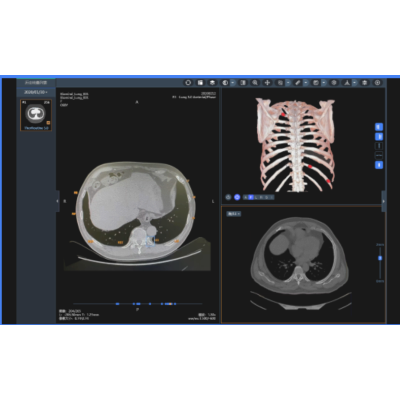

肋骨影像智能辅助分类诊断

实现细微骨折高敏感识别、多模式骨折精确展示。